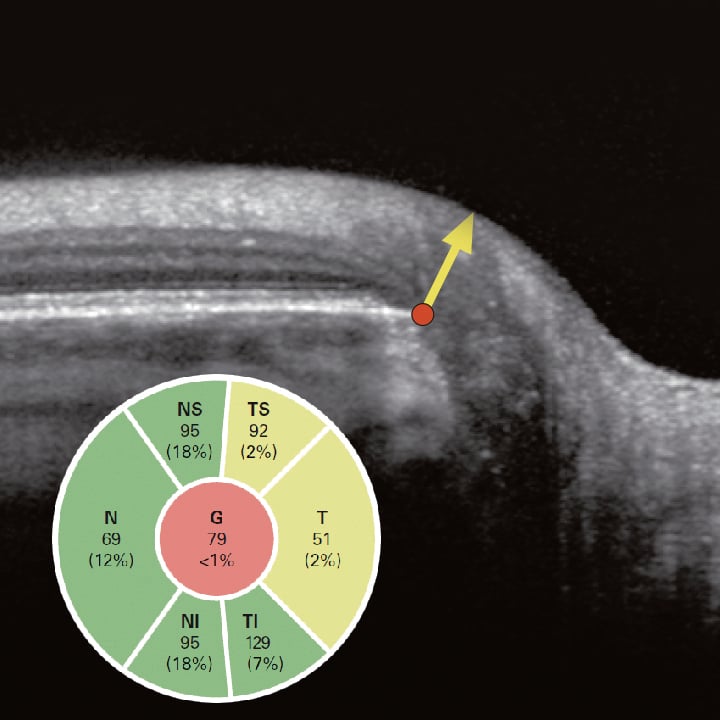

Glaukom-Modul Premium Edition

Die SPECTRALIS Glaukom-Modul Premium Edition bietet eine umfassende, personalisierte Analyse des Sehnervenkopfes und des Ganglienzellkomplexes, indem einzigartige Scanmuster präzise auf die für die Glaukomdiagnostik relevanten feinen anatomischen Strukturen abgestimmt werden.